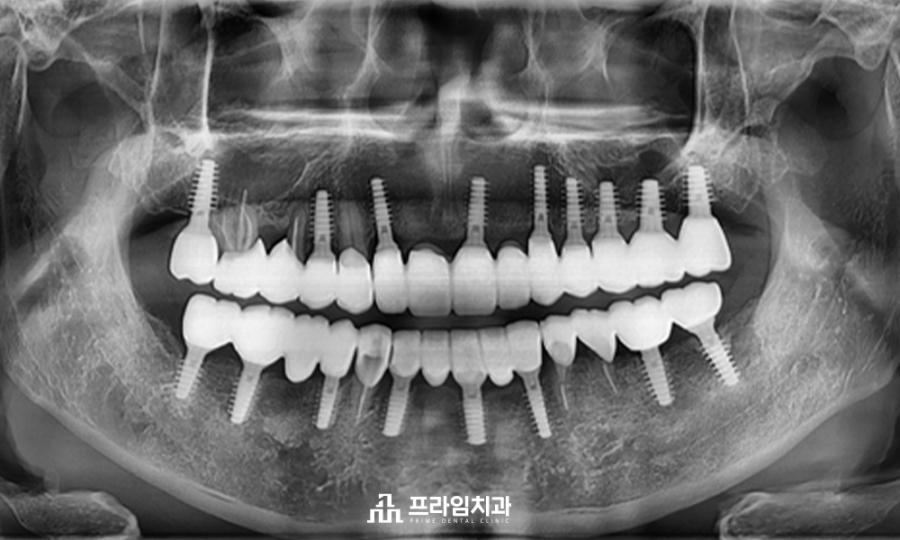

위 환자분은 본원에서 2011년도에 틀니 치료를 받으시고 잘 사용 중이셨습니다. 환자분께서 현재 사용하고 계신 틀니는 잘 맞으며 음식도 너무 잘 드시고 계시는데, 틀니는 아무래도 치아보다 약해 자주 깨지기도 하며 넣고 빼고 하는 부분이 불편해서 임플란트 식립을 생각하고 오셨다고 하셨습니다. 환자분의 엑스레이 사진을 보시면 위아래로 치아는 몇 개 남지 않은 상태입니다. 환자분께서 현재 사용하고 계신 틀니는 이 남아있는 치아에 걸어 사용하는 형태인 부분틀니입니다.

부분틀니를 걸며 힘이 많이 가해져 손상을 입은 치아는 자연치아를 최대한 살려 근관치료와 치관확장술을 진행하였으며, 치아가 없는 부위에는 위쪽 9개, 아래쪽 8개의 임플란트 식립으로 전체적으로 이상적인 교합을 맞추어 치료를 마무리하였습니다.

남아있는 치아 위에 씌운 크라운 보철물의 경우, 부분 틀니에 맞춰 제작이 되어 있어 위아래의 교합을 정교하게 맞추기 위해 새로 크라운 보철물을 제작하였습니다.

위의 사진은 임플란트 식립 후 5년 후의 정기 검진 시 사진입니다.

프라임치과의 최소침습 임플란트 식립과 더불어 환자분께서 관리도 잘 해주셔서 건강하게 유지가 잘 되고 있는 모습입니다.